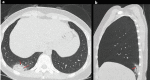

A new type of coronavirus (2019-nCoV) is rapidly spreading worldwide and causes pneumonia, respiratory distress, thromboembolic events, and death. Chest computed tomography (CT) plays an essential role in the diagnosis of viral pneumonia, monitoring disease progression, determination of disease severity, and evaluating therapeutic efficacy. Chest CT can show important clues of 2019-nCoV disease (also known as COVID-19) in patients with an appropriate clinic. Prompt diagnosis of COVID-19 is essential to prevent disease transmission and provides close clinical observation of patients with clinically severe disease. Therefore, radiologists and clinicians should be familiar with the CT imaging findings of COVID-19 pneumonia. Herein, we aimed to review the imaging findings of COVID-19 pneumonia and examine the critical points to be considered for imaging in cases with COVID-19 suspicion.